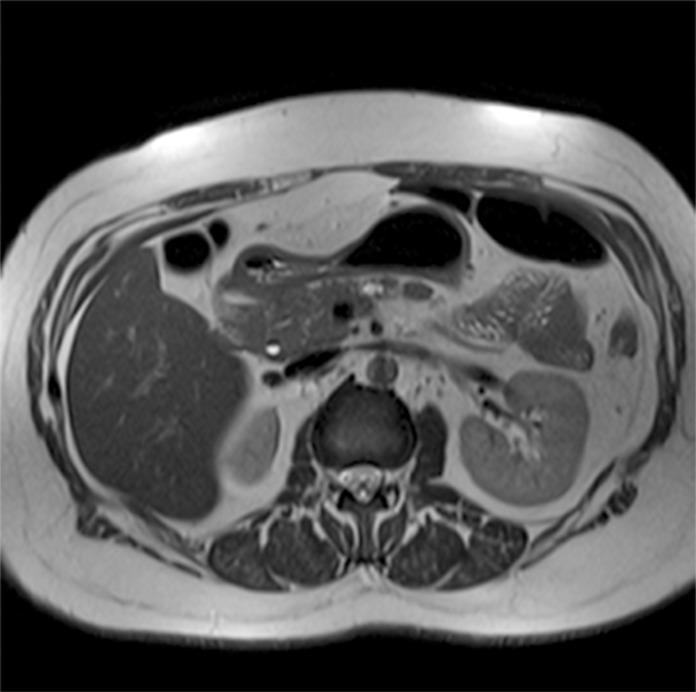

3特斯拉磁共振成像中偶然发现的胰腺囊肿的患病率

Prevalence of incidental pancreatic cysts on 3 tesla magnetic resonance.

To ascertain the prevalence of pancreatic cysts detected incidentally on 3-Tesla magnetic resonance imaging (MRI) of the abdomen and correlate this prevalence with patient age and gender; assess the number, location, and size of these lesions, as well as features suspicious for malignancy; and determine the prevalence of incidentally detected dilatation of the main pancreatic duct (MPD).

Retrospective analysis of 2,678 reports of patients who underwent abdominal MRI between January 2012 and June 2013. Patients with a known history of pancreatic conditions or surgery were excluded, and the remaining 2,583 reports were examined for the presence of pancreatic cysts, which was then correlated with patient age and gender. We also assessed whether cysts were solitary or multiple, as well as their location within the pancreatic parenchyma, size, and features suspicious for malignancy. Finally, we calculated the prevalence of incidental MPD dilatation, defined as MPD diameter ≥ 2.5 mm.

Pancreatic cysts were detected incidentally in 9.3% of patients (239/2,583). The prevalence of pancreatic cysts increased significantly with age (p<0.0001). There were no significant differences in prevalence between men and women (p=0.588). Most cysts were multiple (57.3%), distributed diffusely throughout the pancreas (41.8%), and 5 mm or larger (81.6%). In 12.1% of cases, cysts exhibited features suspicious for malignancy. Overall, 2.7% of subjects exhibited incidental MPD dilatation.

In this sample, the prevalence of pancreatic cysts detected incidentally on 3T MRI of the abdomen was 9.3%. Prevalence increased with age and was not associated with gender. The majority of cysts were multiple, diffusely distributed through the pancreatic parenchyma, and ≥ 5 mm in size; 12.1% were suspicious for malignancy. An estimated 2.7% of subjects had a dilated MPD.